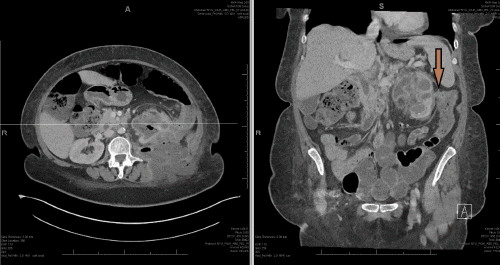

Figure 3. Left Nephrostomy Tube in Good Position and Widely Patent. Published with Permission

Poor output likely secondary to obstructive nature of staghorn calculus with isolated infundibulum